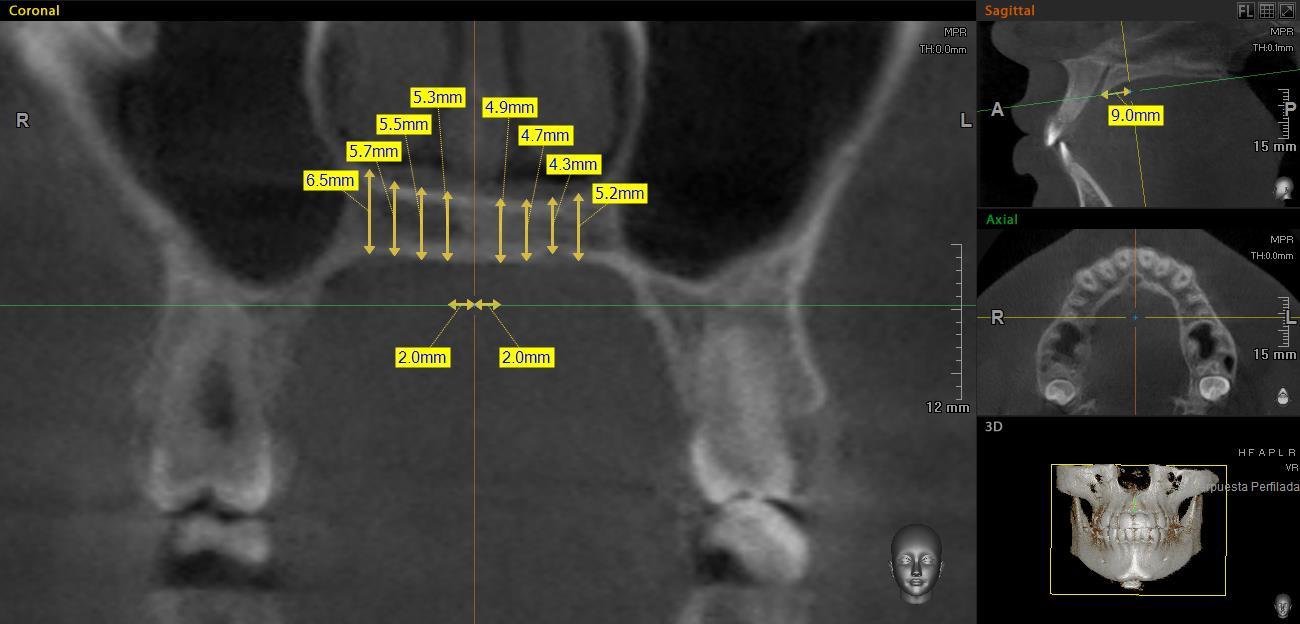

En el corte sagital, las mediciones se realizaron de los 0 a los 24mm, con intervalos de 3 mm entre cada una, con la primera medición en el borde posterior del foramen incisivo (Figura 2). Las mediciones del grosor palatino se realizaron en el corte coronal a los 2, 4, 6 y 8mm, de la sutura media palatina hacia ambos lados (Figura 3).

Posteriormente, en el corte coronal (Figura 3), perpendicular al plano axial se tomaron las medidas del grosor palatino en cada uno de los puntos de intersección de las líneas de referencia antes mencionadas, formando una cuadrícula de 72 sitios (Figura 4). Así, en las Figuras 3 y 4 se observa el grosor palatino de 5.3mm a los 2mm (sagital) y 9mm (coronal) del lado derecho.

Grosor palatino medido a los 9mm del borde posterior del foramen incisivo

Cuadrícula del paladar. Grosor palatino de 5.3mm a los 2mm (sagital) y 9mm (coronal) del lado derecho